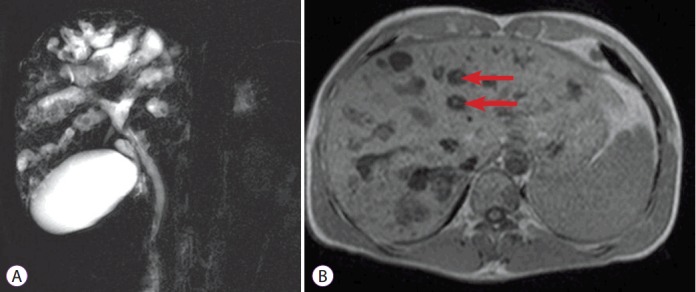

Tomografia computadorizada mostrando dilatações biliares com o “sinal do ponto central” (setas), que correspondem a veias portais e artérias hepáticas (fonte)

Colangiorressonância mostrando múltiplas dilatações irregulares com o típico “sinal do ponto central” e presença de cálculos (fonte)